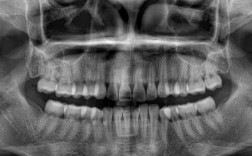

- 带上你的口腔X光片(如全景片、CBCT)。